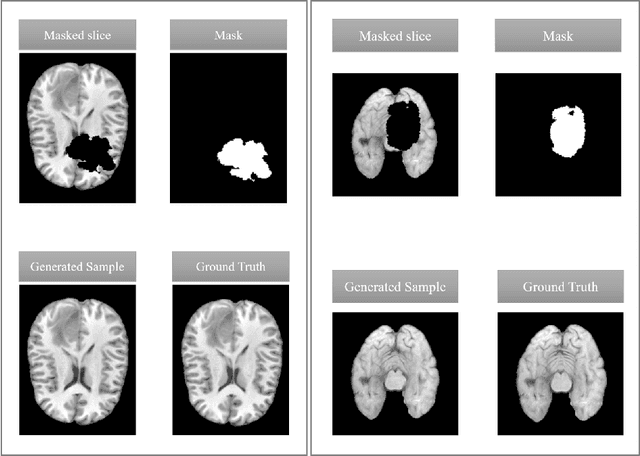

Abstract:This paper is a contribution to the "BraTS 2023 Local Synthesis of Healthy Brain Tissue via Inpainting Challenge". The task of this challenge is to transform tumor tissue into healthy tissue in brain magnetic resonance (MR) images. This idea originates from the problem that MR images can be evaluated using automatic processing tools, however, many of these tools are optimized for the analysis of healthy tissue. By solving the given inpainting task, we enable the automatic analysis of images featuring lesions, and further downstream tasks. Our approach builds on denoising diffusion probabilistic models. We use a 2D model that is trained using slices in which healthy tissue was cropped out and is learned to be inpainted again. This allows us to use the ground truth healthy tissue during training. In the sampling stage, we replace the slices containing diseased tissue in the original 3D volume with the slices containing the healthy tissue inpainting. With our approach, we achieve comparable results to the competing methods. On the validation set our model achieves a mean SSIM of 0.7804, a PSNR of 20.3525 and a MSE of 0.0113. In future we plan to extend our 2D model to a 3D model, allowing to inpaint the region of interest as a whole without losing context information of neighboring slices.